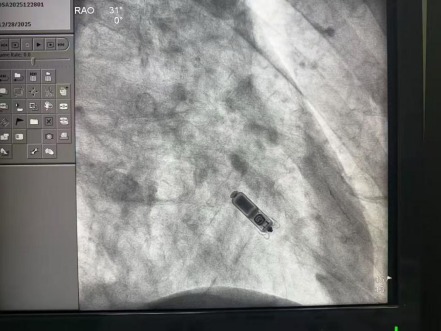

专家团队通过右侧股静脉穿刺,将仅如维生素胶囊大小的Micra起搏器,通过微创递送系统精准送达右心室理想位置。并确认起搏器定位精准、固定牢固、感知灵敏,阻抗正常。

手术图片